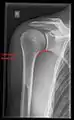

X-ray

Projectional radiography views of the shoulder include:

AP-projection 40° posterior oblique after Grashey

The body has to be rotated about 30 to 45 degrees towards the shoulder to be imaged, and the standing or sitting patient lets the arm hang. This method reveals the joint gap and the vertical alignment towards the socket.[24]

Transaxillary projection

The arm should be abducted 80 to 100 degrees. This method reveals:[24]

• The horizontal alignment of the humerus head in respect to the socket and the lateral clavicle in respect to the acromion

• Lesions of the anterior and posterior socket border, or of the tuberculum minus

• The eventual non-closure of the acromial apophysis

• The coraco-humeral interval

Y-projection

The lateral contour of the shoulder should be positioned in front of the film in a way that the longitudinal axis of the scapula continues parallel to the path of the rays. This method reveals:[24]

• The horizontal centralization of the humerus head and socket

• The osseous margins of the coraco-acromial arch and hence the supraspinatus outlet canal

• The shape of the acromion

This projection has a low tolerance for errors and, accordingly, needs proper execution.[24] The Y-projection can be traced back to Wijnblath’s 1933 published cavitas-en-face projection.[25]